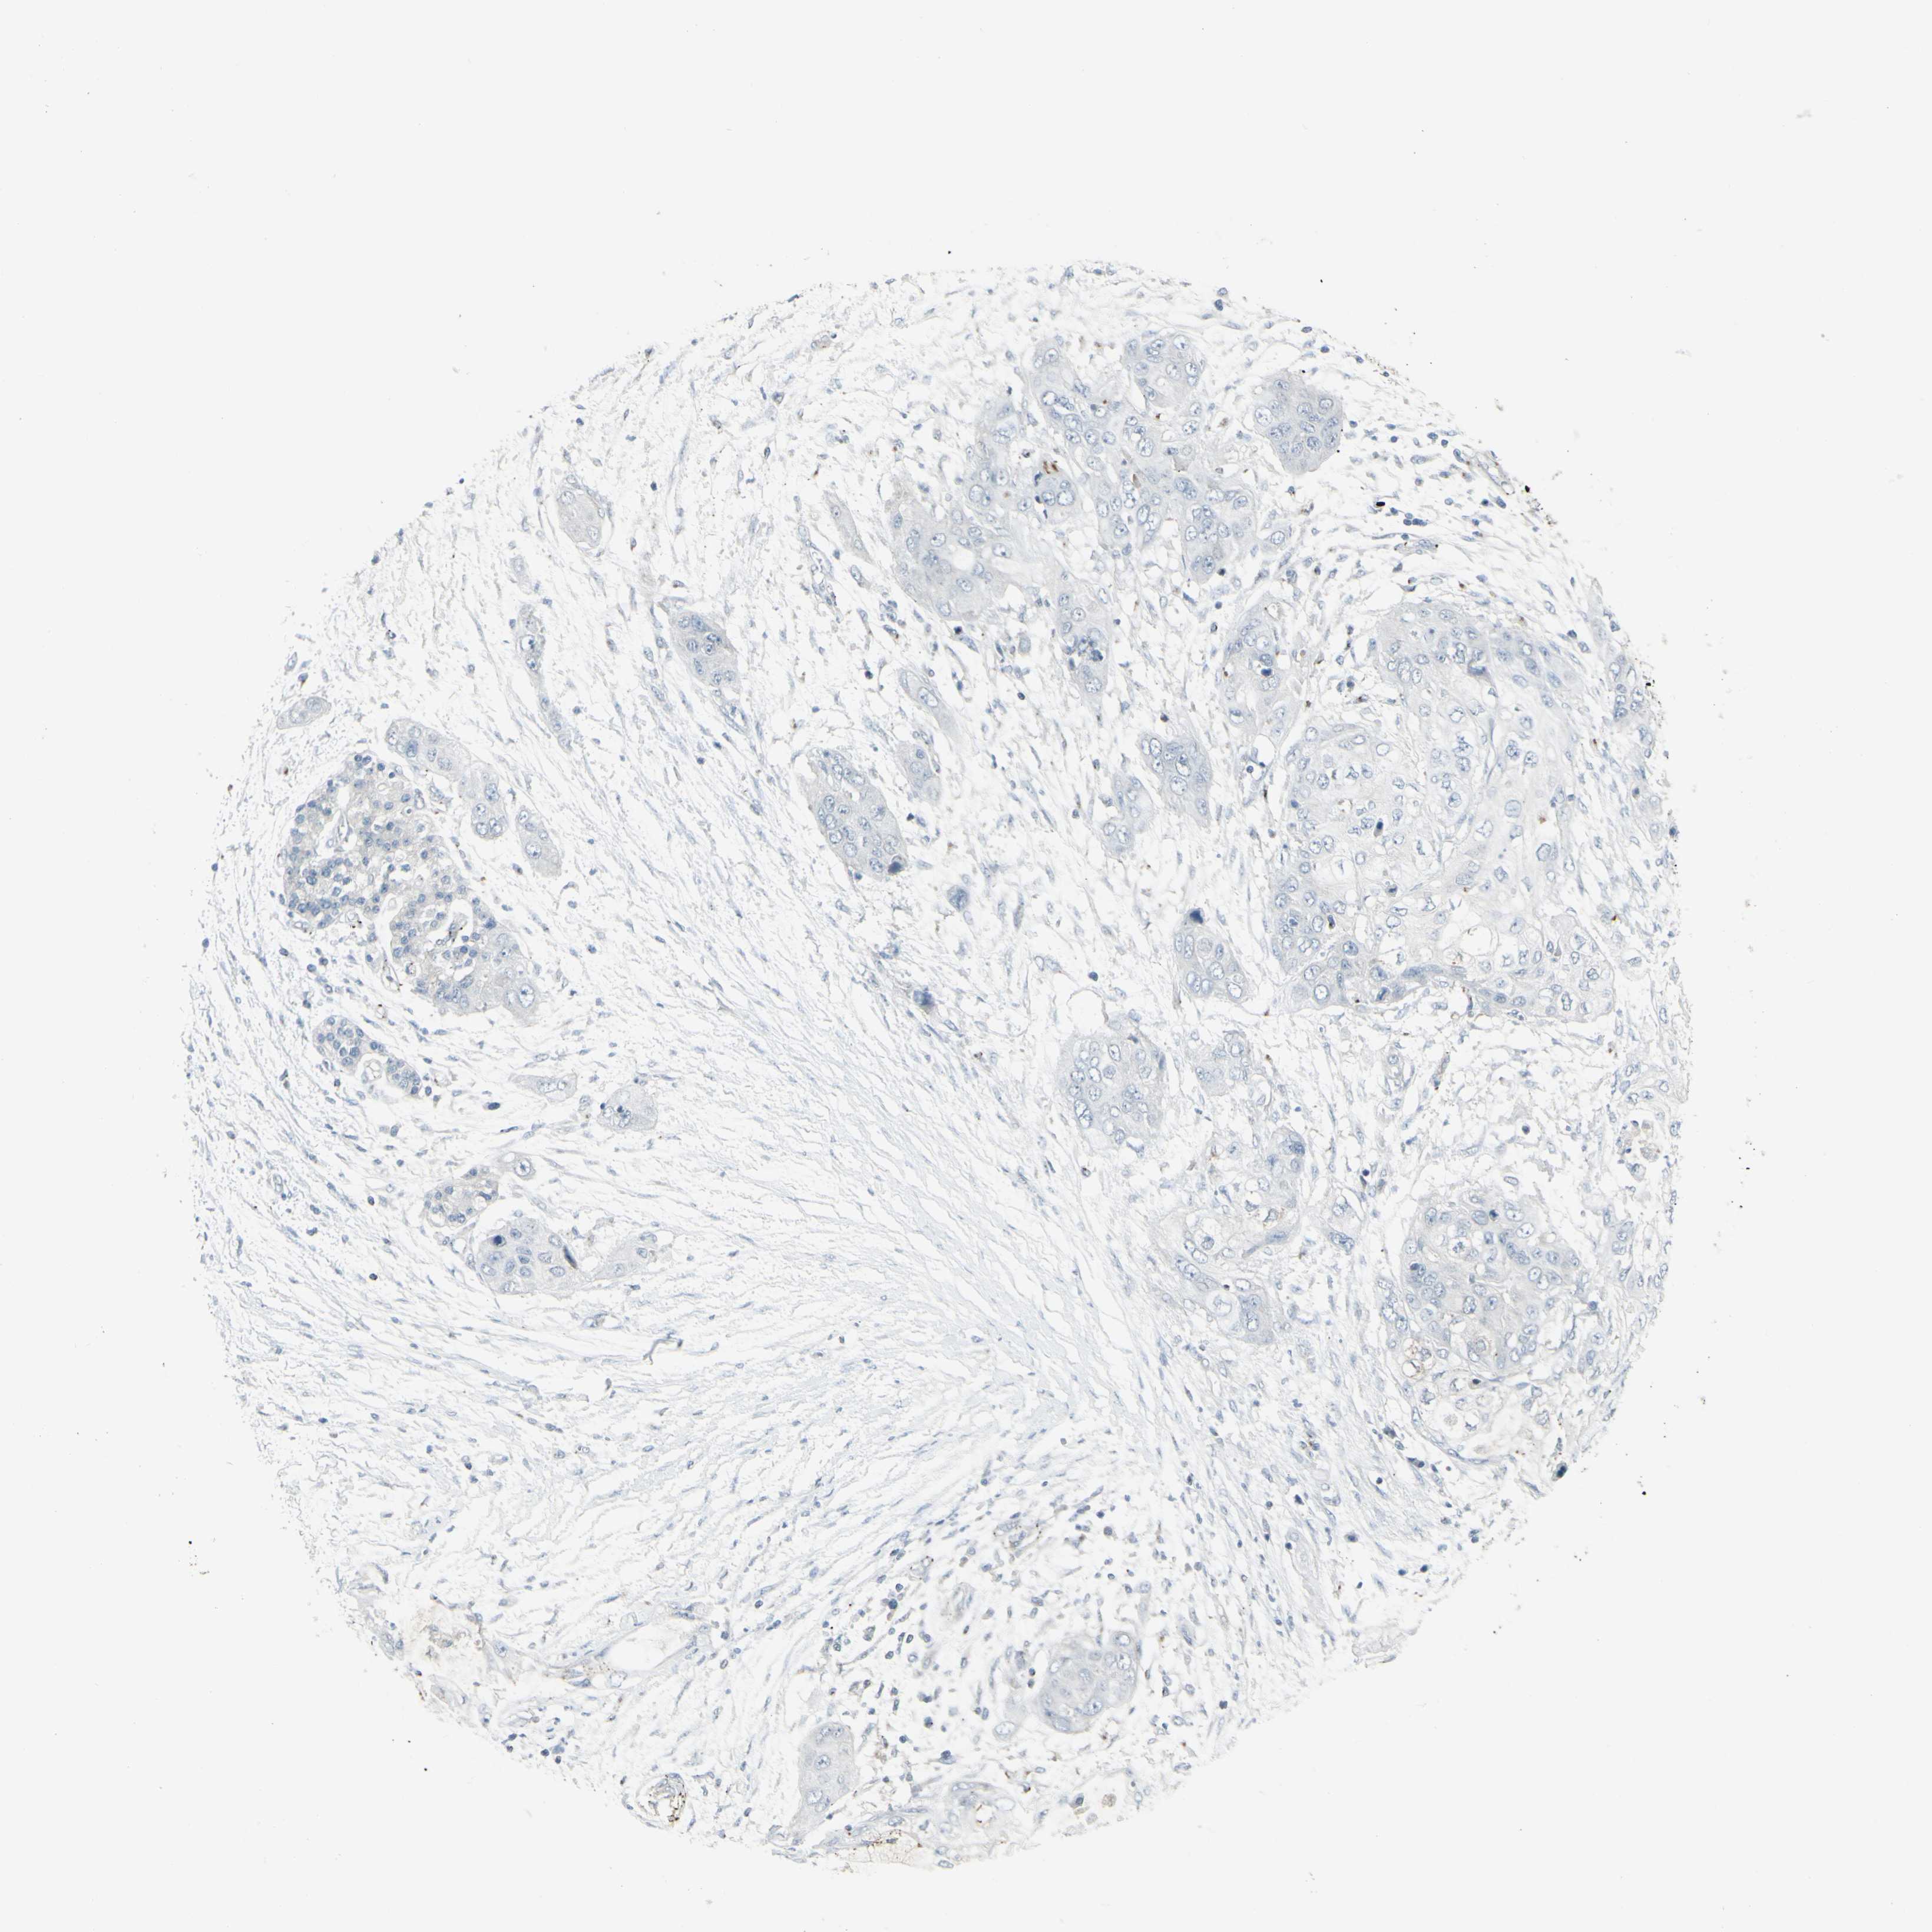

PANCREATIC CANCER - Protein expressioni

A mouse-over function shows sample information and annotation data. Click on an image to view it in a full screen mode. Samples can be filtered based on level of antibody staining by selecting one or several of the following categories: high, medium, low and not detected. The assay and annotation is described here.

Note that samples used for immunohistochemistry by the Human Protein Atlas do not correspond to samples in the TCGA dataset.

Antibody stainingi

Antibody staining in the annotated cell types in the current human tissue is reported as not detected, low, medium, or high, based on conventional immunohistochemistry profiling in selected tissues. This score is based on the combination of the staining intensity and fraction of stained cells.

Each image is clickable and will lead to virtual microscopy that enables deeper exploration of all samples and also displays staining intensity scores, fraction scores and subcellular localization as well as patient and tissue information for each sample.

Antibody HPA011762

Antibody HPA017086

Staining

High

Medium

Low

Not detected

Intensity

Strong

Moderate

Weak

Negative

Quantity

>75%

75%-25%

<25%

None

Location

Nuclear

Cytoplasmic/membranous

Cytoplasmic/membranous,nuclear

Adenocarcinoma, NOS

Adenocarcinoma, metastatic, NOS